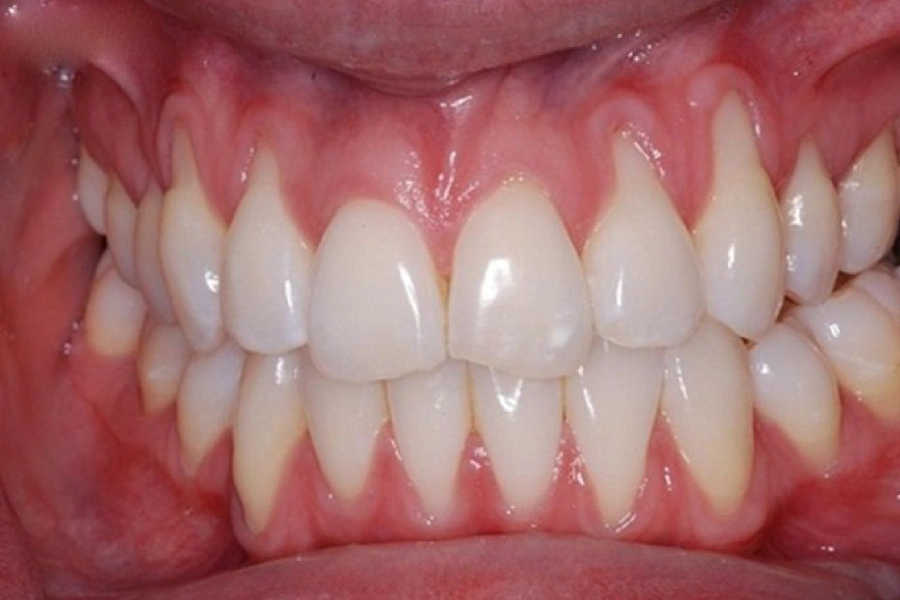

Ở trạng thái khỏe mạnh, nướu có màu hồng nhạt, săn chắc, ôm sát quanh răng.

Khi mắc bệnh nha chu, nướu sẽ chuyển sang màu đỏ sẫm, mềm, dễ chảy máu khi chạm nhẹ.

Xương ổ răng dần tiêu đi, tạo thành khoảng hở giữa răng và nướu, khiến vi khuẩn tiếp tục xâm nhập sâu hơn.

Sự thay đổi này diễn ra chậm rãi nên nhiều người không nhận ra cho đến khi bệnh đã tiến triển nặng.